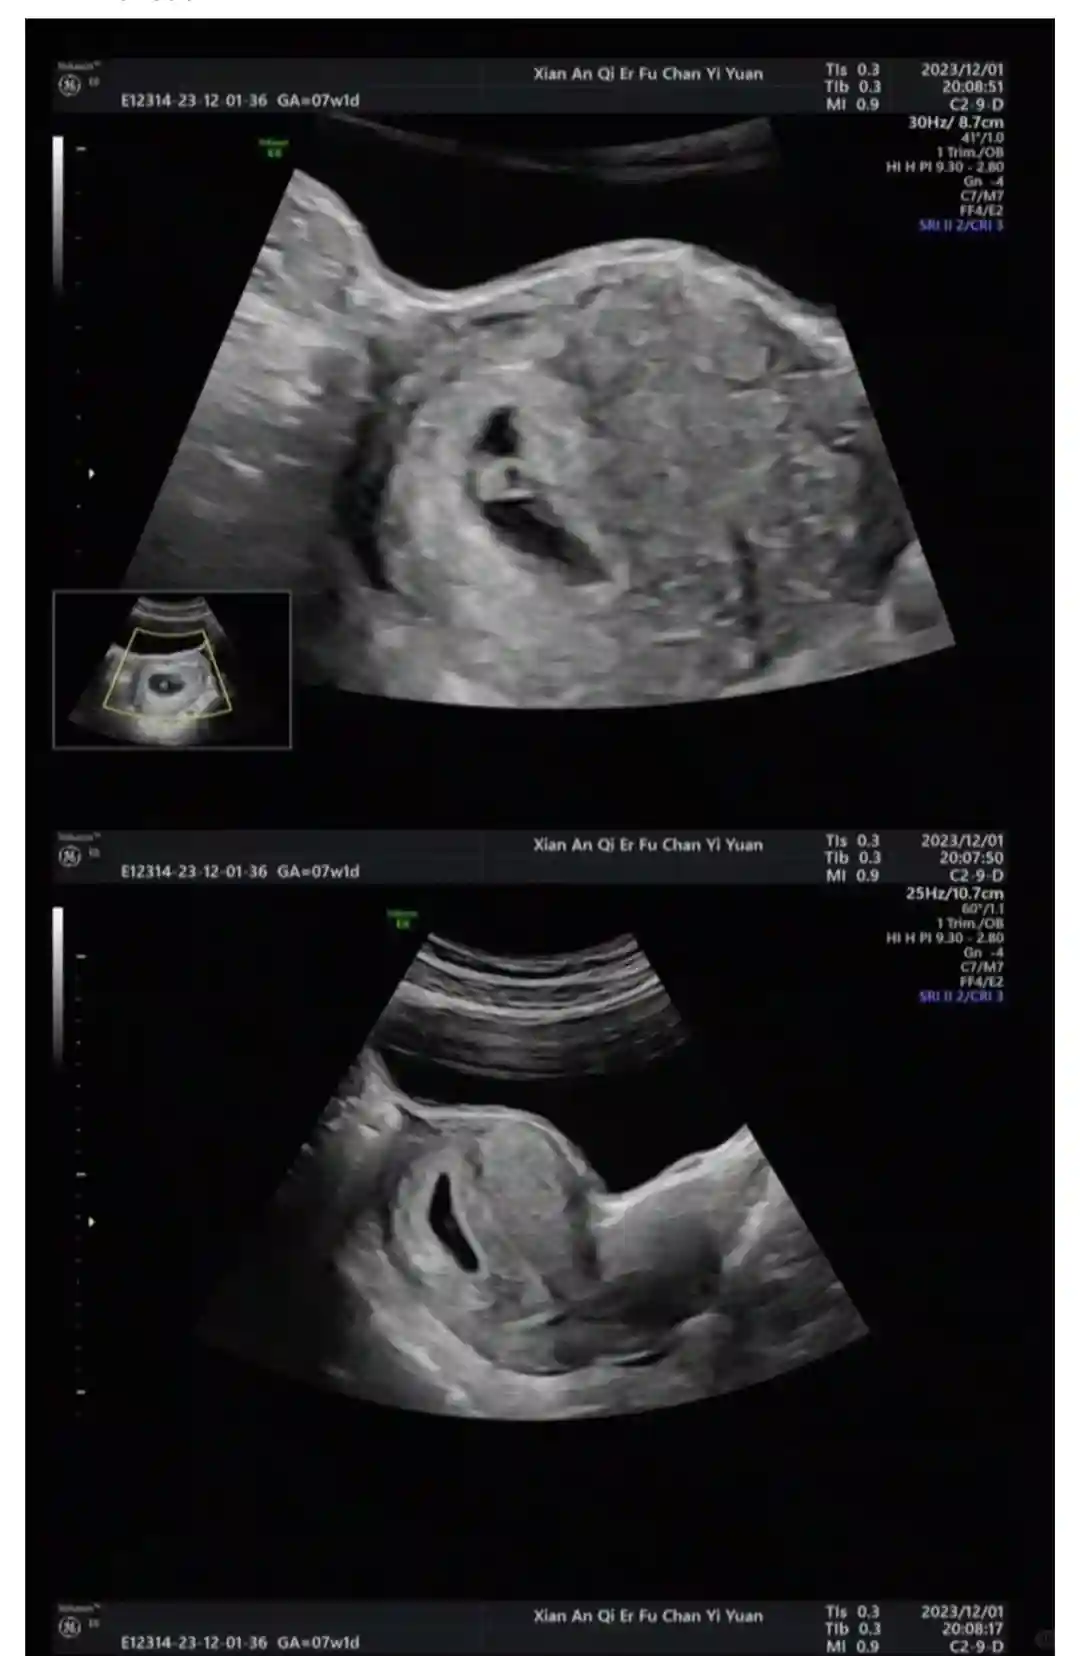

在建档前的每次B超和抽血我都是选择安琪儿的夜间门诊,这样不影响白天上班,不需要频繁请假。建档后的产检我周内去过,但大部分都是周末去的。我当时的医生是张培莲医生,张主任的门诊时间是周一四六,公众号上每周会有推送各位医生的门诊时间,很方便。第一次去的时候和销售联系好时间,全程她会带着你,非常方便。之后每次检查完医生会直接预约好下一次的产检时间,到时候直接去挂号就可以。周内人很少,我每次周六早上去人会稍微多一些,但和公立医院相比还是少很多很多的,我基本每次检查都在两个小时内搞定,家属也可以全程陪同,孩子爸爸也可以每一次都看到宝宝B超的变化。每次检查的前一天医院的工作人员会提醒,并会说需不需要空腹。所有的工作人员态度都非常好,医生的态度也是,有问必答,非常有耐心。